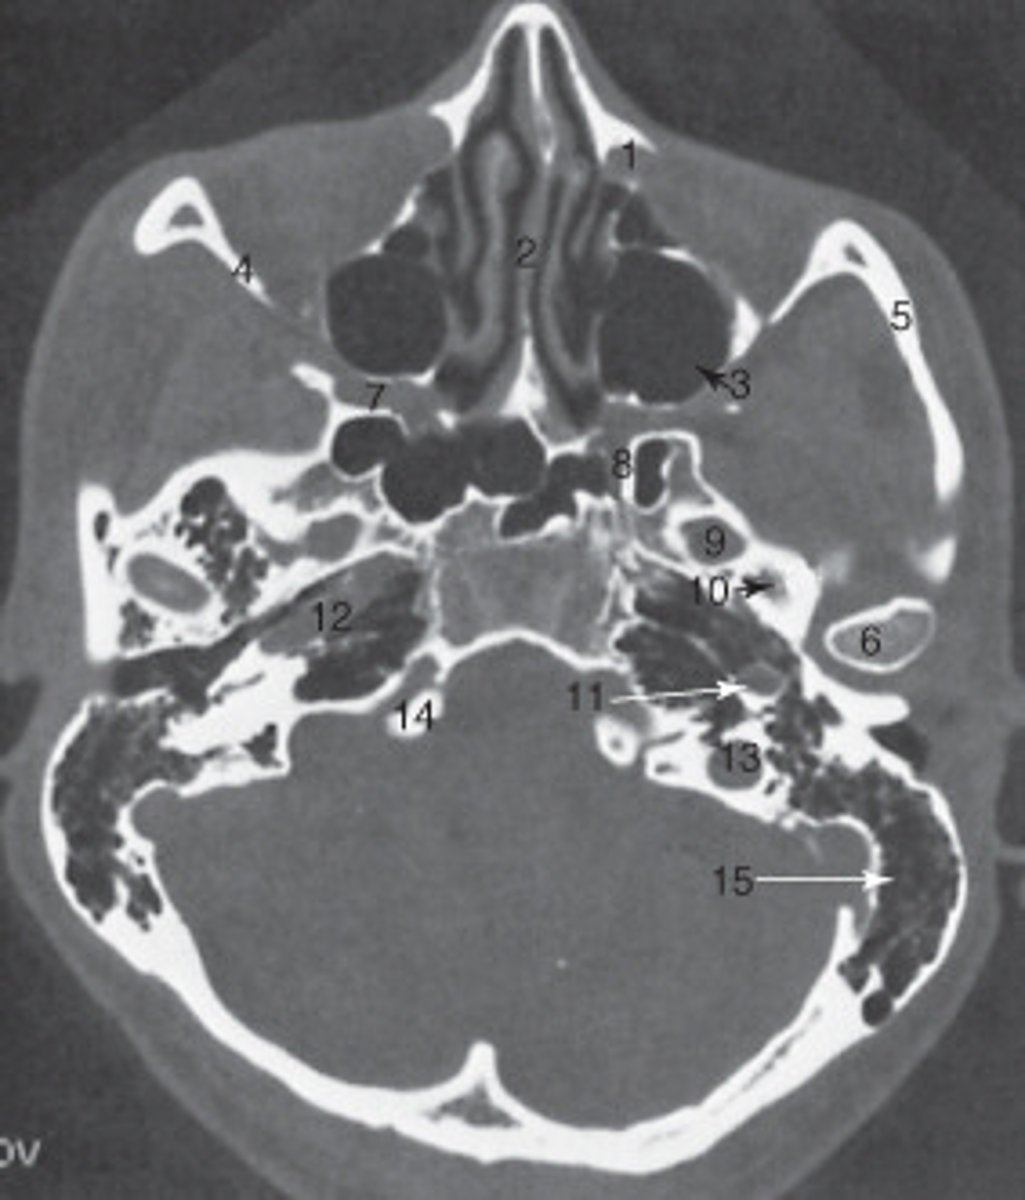

15

the mastoid air cells are labeled:

manidubular condyle

the structure labeled 6 is the:

zygomatic arch

the structure labeled 5 is the:

2

the ethmoid sinuses are labeled:

The sphenoid sinus is labeled:

<p>The sphenoid sinus is labeled:</p>

internal carotid artery

the structure labeled as 8 is the: